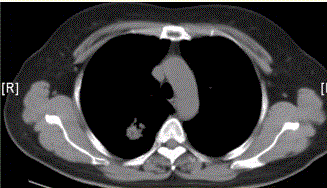

问题 患者女,54岁,无症状,常规体检透视时发现右上肺阴影。既往无结核病史。体格检查阴性。CT结果如下图。 本病例可见的征象包括

选项 A.分叶征 B.毛刺征 C.胸膜凹陷征 D.空泡征 E.含气支气管征 F.钙化

答案 ABCE

解析 ABCE